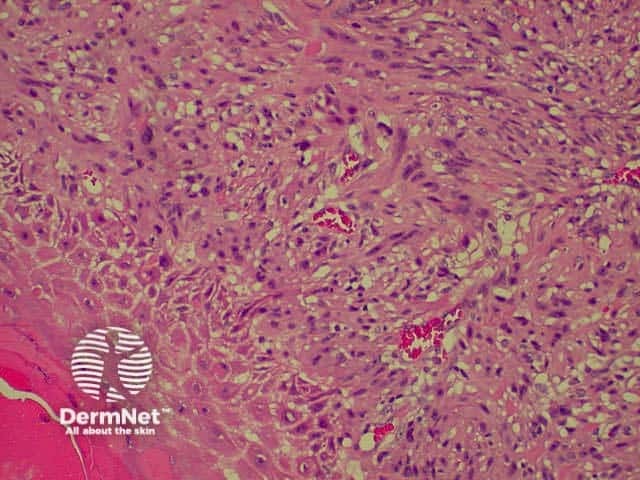

This is a tumour that has conflicting clinical and histological features. Clinically, this is a tumour of the elderly arising in sun damaged skin. Histologically, there is severe nuclear atypia with many mitotic figures and features of a sarcoma located in the superficial and mid dermis.

The histological diagnosis is one of exclusion following immunohistochemistry, as spindle cell squamous carcinomas, melanomas and leiomyosarcomas may all appear similar. It is possible that this lesion's good prognosis is simply due tits superficial location, rather than its cell of origin, but the features are well recognised and the prognosis well documented so that its retention as a specific entity appears justified.

pathology of atypical fibroxanthoma